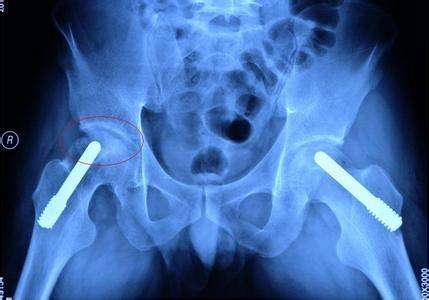

股骨头坏死患者肌肉萎缩主要是因为大腿的血液供应减少造成的。股骨头坏死的发生虽然原因各个有不同,但是发病肌机理都是导致股骨头周围血液循环障碍。

血液循环障碍不但会造成股骨头坏死,同时还会造成骨动脉都下肢广泛组织的血液供应减少,下肢肌肉长时间营养不良,就会造成下肢肌肉萎缩。第二种原因是,患肢大腿由于疼痛不经常走路负重,肌肉长时间得不到有效的锻炼肌肉不再发育,肌肉逐渐萎缩变小,造成的废用性肌肉萎缩。

对于股骨头坏死所导致的肌肉萎缩,其实并非都能恢复。之所以同样是肌肉萎缩,有的人能恢复,有的人不能恢复的问题,主要原因出在股骨头坏死的程度上。中早期股骨头坏死股骨头外形多大的破坏,修复后股骨头外形基本正常,不影响走路功能,将来病人走路距离不受影响,负重也不受影响。同时早期股骨头坏死血液循环破坏也不严重,通过治疗可以恢复,下肢血液供应不受影响,股动脉完全能够满足下肢用血液的需要,这样通过锻炼下肢肌肉萎缩可以恢复。

中晚期股骨头坏死就不一样了,股骨头塌陷严重,股骨头外形无法恢复,髋关节功能无法恢复,行走距离不能达到正常。股骨头周围血管部分消失终身不能恢复,下肢血运循环不能满足肌肉发育的需要,肌肉在缺乏血液营养的条件下不可能正常发育,这样一部分股骨头坏死患者的下肢肌肉萎缩就不可能恢复。